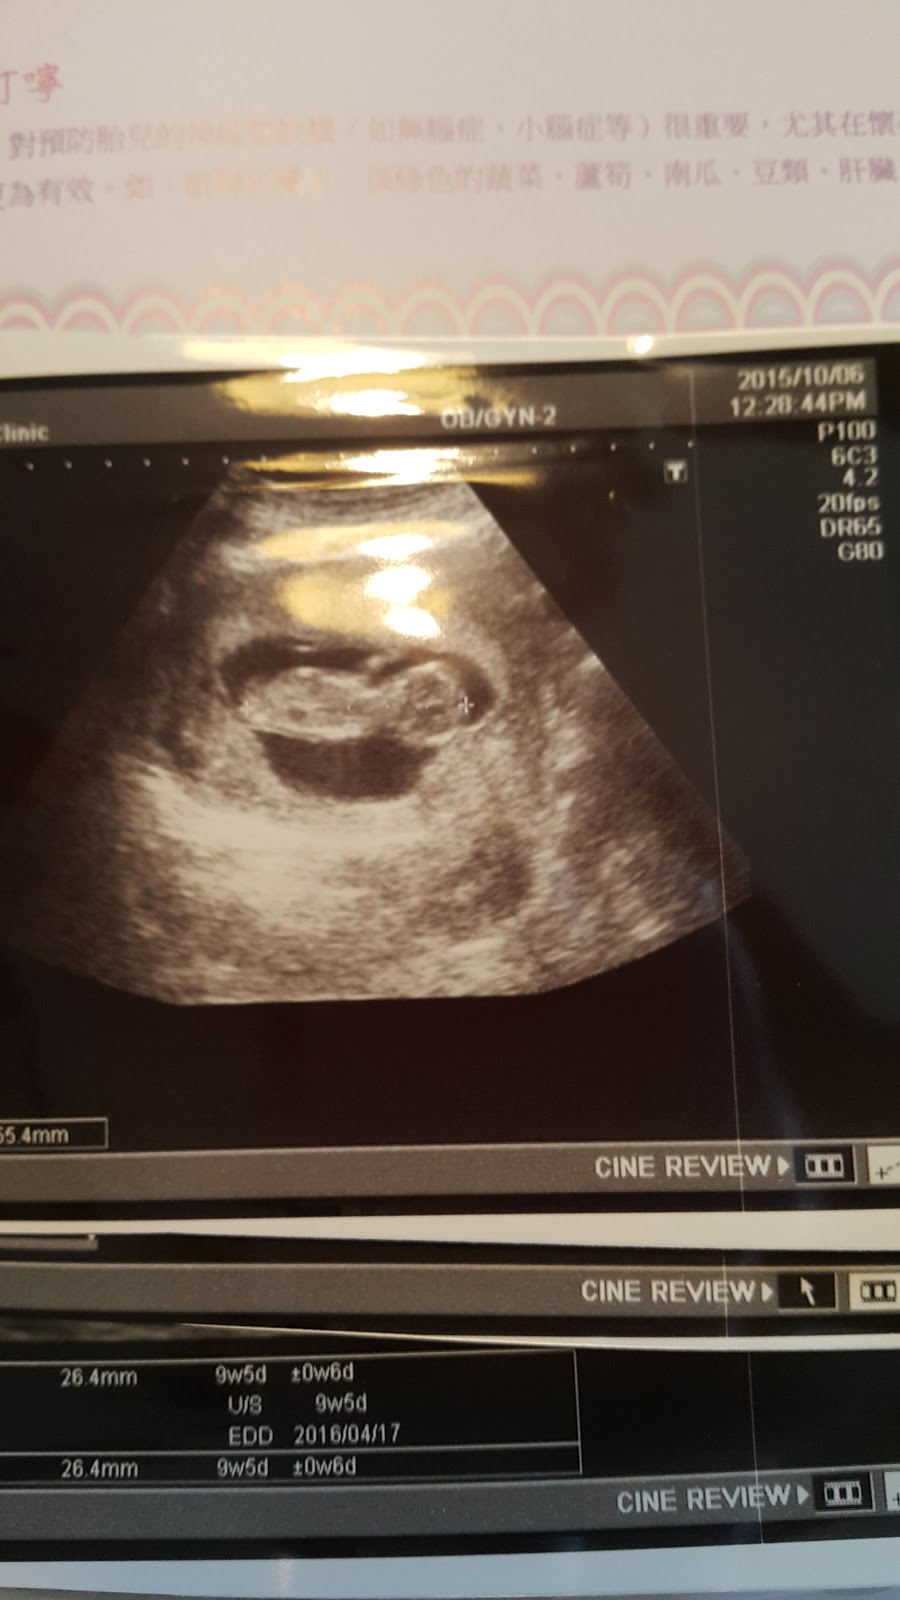

有時候認真把超音波照片拍下來與寫文章,除了記錄也是保存超音波照片的好方法吧!

接近中午,終於輪到我,醫生熱情的打招呼真的讓我安心不少,先是看了報告,報告一切正常,然後按例先照了超音波,寶寶真的有在好好長大!

這次看到更清楚的模樣了,手腳也很清楚,還看到寶寶在動,醫生說是個活潑的寶寶,看他在肚子裡動來動去的模樣,真的可愛極了!